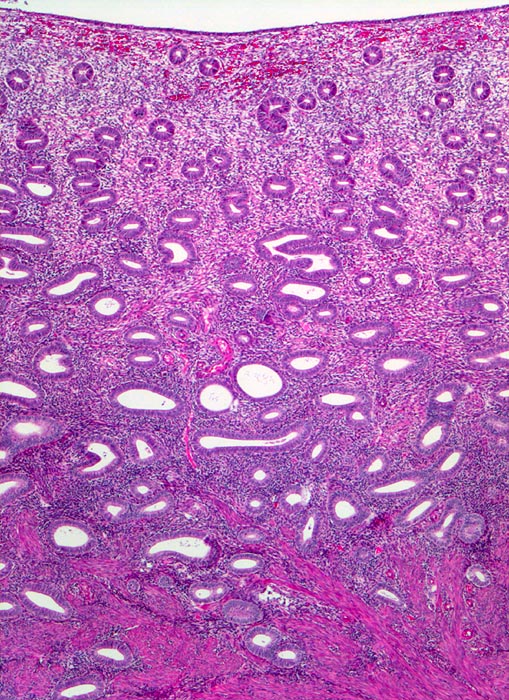

späte Proliferationsphase

Endometrium

Hoch aufgebautes Endometrium mit kleinen rundlichen Drüsen und zelldichtem Stroma. Das Endometrium bildet zungenförmige Ausläufer in das darunterliegende Myometrium.

Dysfunktionelle Blutungen bei Uterus myomatosus.

Histologie

25